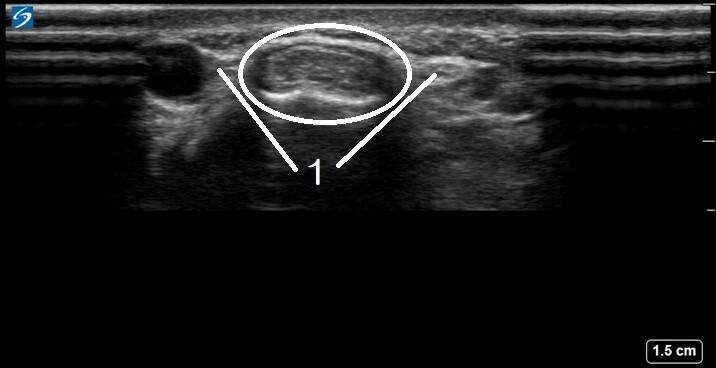

1. Superficial Branches of the Radial Nerve

Circled: Compartment 1 - Abductor Pollicis Longus and Extensor Pollicis Brevis